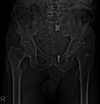

Abstract Image